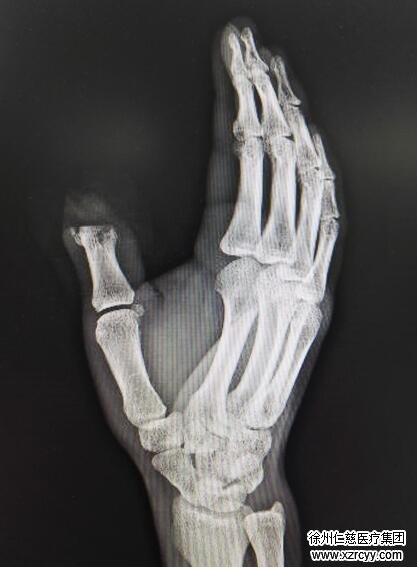

患者术前X线

“把我的脚趾变成手指头?”张华头一次听到有这样的手术,虽然心里觉得有点别扭,但他最后还是听从了潘勇的建议。手术进行了整整8个小时,当取下足趾移植时,潘勇先分别固定足趾截取的趾骨和拇指残留的近节指骨,用克氏针交叉固定,然后将足趾肌腱、神经及血管与手指缝合。

潘勇说,手术最难的其实就是血管吻合部分,每根血管的外径只有0.4毫米—0.5毫米,借助显微镜每根血管上要缝4针—6针。张华的大拇指本来就比较粗,大脚趾移植上去后,看起来几乎可以“以假乱真”。